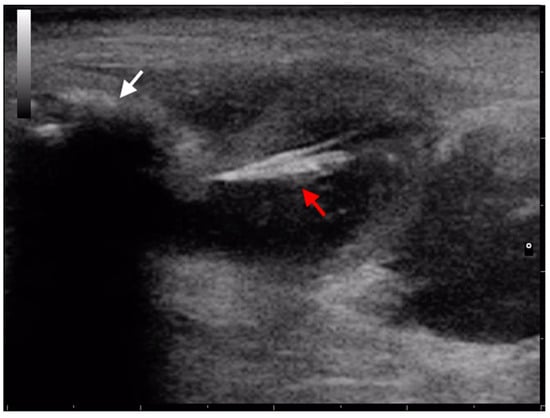

- Gnudi, G.; Volta, A.; Bonazzi, M.; Gazzola, M.; Bertoni, G. Ultrasonographic features of grass awn migration in the dog. Vet. Radiol. Ultrasound 2005, 46, 423–426. [Google Scholar] [CrossRef]

- Della Santa, D.; Rossi, F.; Carlucci, F.; Vignoli, M.; Kircher, P. Ultrasound-guided retrieval of plant awns. Vet. Radiol. Ultrasound 2008, 49, 484–486. [Google Scholar] [CrossRef] [PubMed]

- Fauchon, E.; Lassaigne, C.; Ragetly, G.; Gomes, E. Ultrasound-guided removal of vegetal foreign bodies in the lower extremities of dogs: A retrospective study of 19 cases. Vlaams Diergeneeskd. Tijdschr. 2017, 86, 285–290. [Google Scholar] [CrossRef]

- Manfredi, S.; Covi, G.; Bonazzi, M.; Gnudi, G.; Fumeo, M.; Miduri, F.; Daga, E.; Volta, A. Ultrasound-guided removal of soft tissue foreign bodies in companion animals: A case series. Vet. Med. 2020, 65, 49–55. [Google Scholar] [CrossRef]